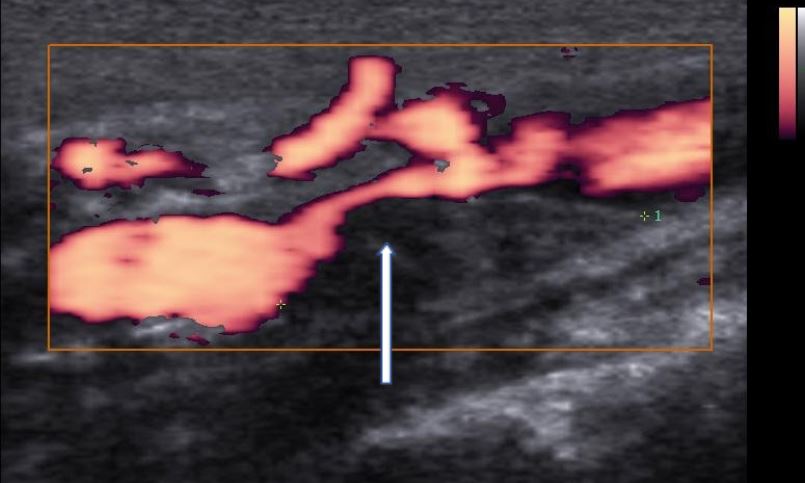

Doppler de carótidas e vertebrais e placas de gordura

Quando são identificadas pelo Doppler de carótidas e vertebrais placas de gordura no interior das artérias, não se deve realizar a medida da espessura mediointimal.

O risco de doenças coronarianas e de AVC  nesta situação é maior que o risco de uma medida da espessura mediointimal aumentada, pois a aterosclerose já está presente e quanto mais placas de gordura identificadas no exame, maior o risco.

Na presença de placas de gordura que determinam uma obstrução significativa, ou se o paciente apresenta sintomas relacionados com a obstrução, recomenda-se o tratamento para desobstruir as artérias, por meio de uma cirurgia aberta (endarterectomia) ou pela colocação de um stent.

Doppler de artérias carótidas e vetebrais

Doppler de carótidas e vertebrais. A seta branca mostra uma placa de gordura que determina obstrução maior que 70% na artéria carótida interna.

O ideal é identificar as pessoas de risco antes do desenvolvimento da aterosclerose por meio da medida da espessura mediointimal, por dados clínicos, laboratoriais e antecedentes familiares.